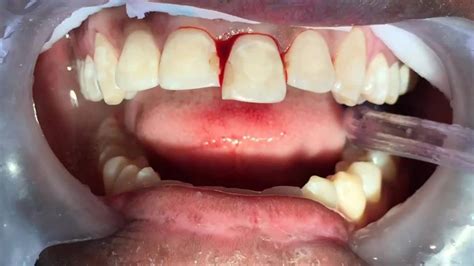

- Extrusión: Cursa con un desplazamiento del diente en dirección a incisal.

- INMOVILIZACIÓN DE LA PIEZA DENTAL: Al instante de padecer el golpe la pieza dental afectada pasa a la ferulización, con el fin de estabilizar usando alambres o composite.

Según sea el tipo de luxación, la reducción se realizará de diferentes maneras. Incluso en algunos casos (concusión, subluxación) no habrá que realizar maniobras de adaptación. Después de recolocar el diente luxado y antes de proceder a la ferulización, se hará una radiografía para controlar su correcta posición y se evaluará la oclusión.